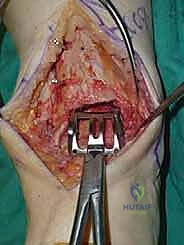

يقوم الدكتور هطيف بعمل شق طولي دقيق في الجزء الأمامي من الكاحل، طوله حوالي 10-15 سم. يتم تشريح الأنسجة بعناية فائقة للوصول إلى المفصل.

* الحماية العصبية الوعائية: هذه هي الخطوة الأكثر حرجاً. يتم تحديد الحزمة الوعائية العصبية (الشريان الظنبوبي الأمامي والعصب الشظوي العميق) وسحبها برفق شديد لحمايتها من أي ضرر جراحي.

3. إزالة النتوءات العظمية وتحضير المفصل (Debridement)

بمجرد كشف المفصل، يقوم الجراح بإزالة الغشاء الزلالي الملتهب والزوائد العظمية (Osteophytes) التي تعيق الحركة. هذه الخطوة ضرورية لاستعادة المعالم التشريحية الطبيعية قبل إجراء القطع العظمي.

4. وضع أدلة القطع (Jig Placement and Alignment)

تعتمد دقة الجراحة على المحاذاة الصحيحة. يتم استخدام أجهزة توجيه متطورة (Jigs) تثبت على عظمة الساق باستخدام دبابيس معدنية. يتم التحقق من صحة الزوايا والمحاور باستخدام جهاز الأشعة السينية المباشر داخل غرفة العمليات (C-arm Fluoroscopy). يضمن الدكتور هطيف أن يكون القطع موازياً للأرض تماماً عند وقوف المريض.

5. القطع العظمي الظنبوبي (Tibial Bone Cut)

باستخدام منشار جراحي دقيق التذبذب، يتم إزالة شريحة رقيقة جداً (بضعة مليمترات) من السطح السفلي التالف لعظمة الظنبوب. يتم القطع بحذر شديد لتجنب إصابة الأوتار الخلفية أو الأوعية الدموية.